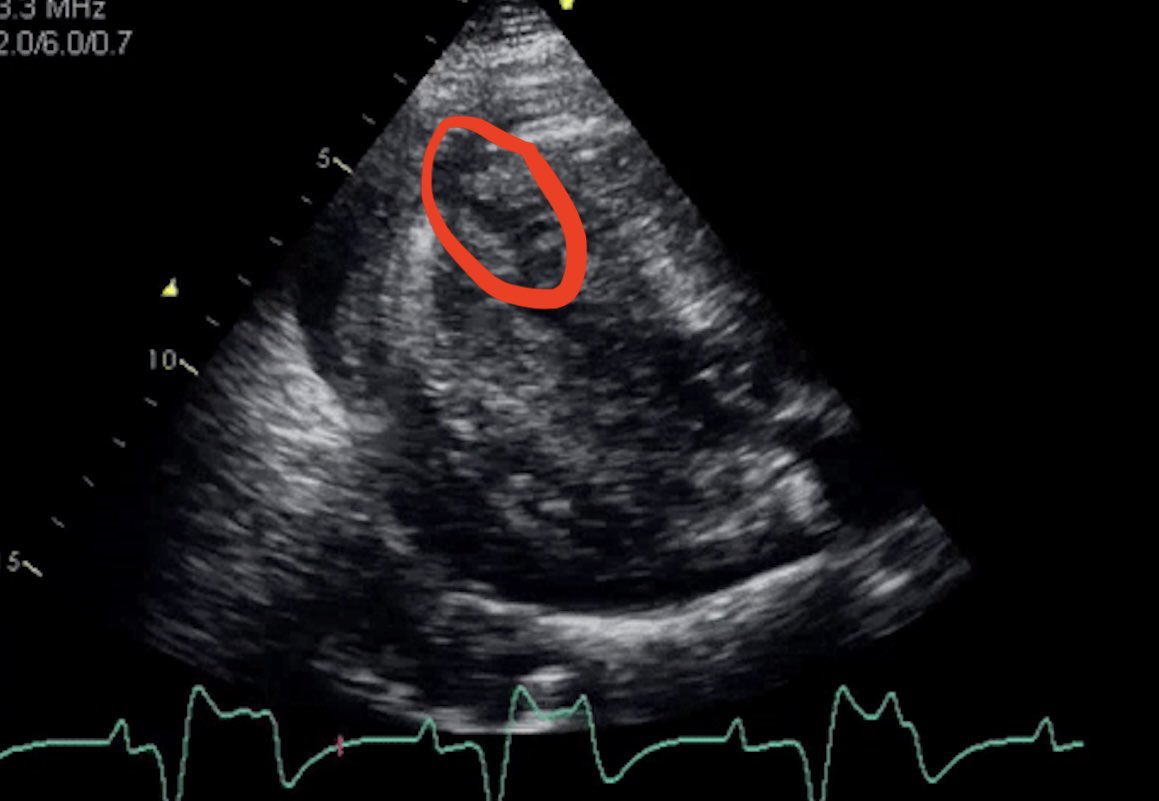

1. Anterior MI (ST elevation on the ECG - not easy to see). 2. Complete heart block. 3. Apical rupture with haemopericardium. No LVH here - this is ‘pseudohypertrophy’ because the LV is so empty - not a surprise given the massive hole! Now…who’s for that beer at @BSEcho?

A little something that everyone wants to see on a Sunday: who can identify three diagnoses in this video? Also (shameless act of promotion alert)….if you get the answer AND come to @BSEcho conference I will personally buy you a beer (other drinks are available🙄)